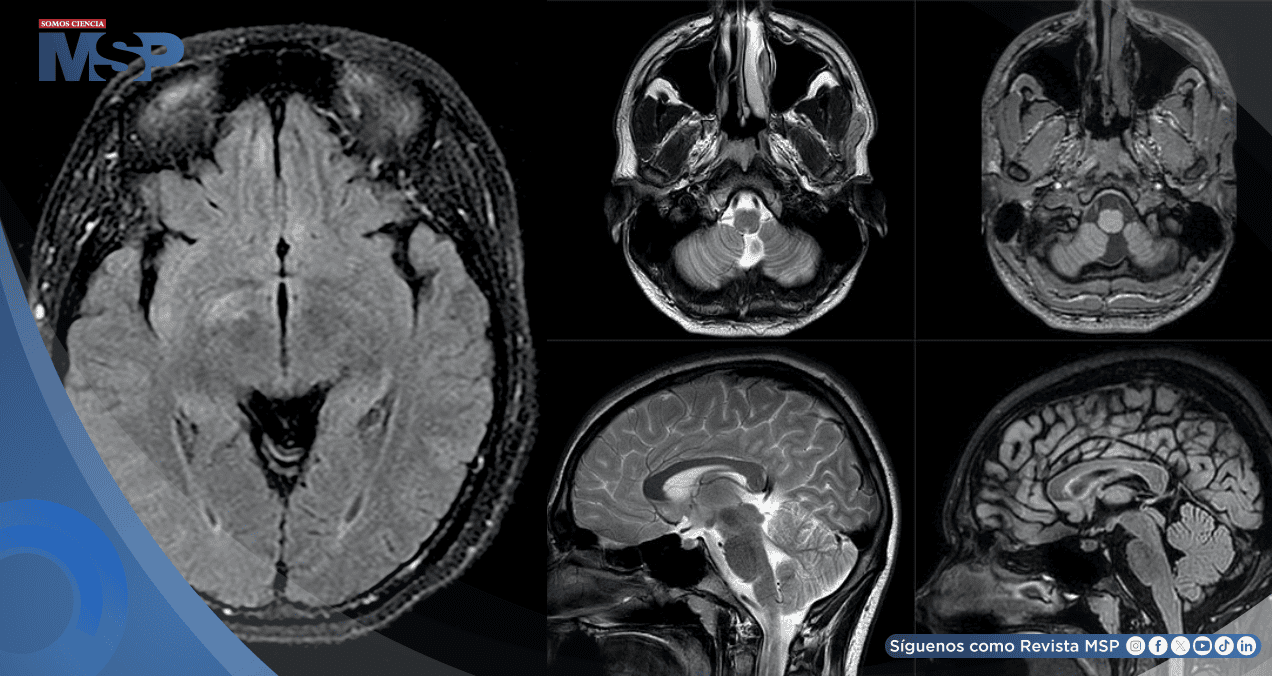

La tomografía computarizada (TC) craneal inicial reveló una hemorragia cerebelosa izquierda. Durante su hospitalización, la paciente desarrolló una pérdida de visión central en el ojo derecho, que describió como un círculo negro. Una resonancia magnética (RM) cerebral confirmó la sospecha clínica al mostrar un realce del nervio óptico derecho, sugestivo de un proceso desmielinizante agresivo.

El estudio se complementó con RM de la columna cervical y torácica, que evidenció un proceso desmielinizante medular central continuo. Con estos hallazgos, la sospecha de un síndrome desmielinizante primario era alta. Se inició tratamiento con metilprednisolona y, de manera crucial, el título de anticuerpos contra la Acuaporina-4 (AQP4), también conocidos como anticuerpos contra la Neuromielitis Óptica (NMO), resultó positivo tras el alta.

Una nueva RM cerebral mostró focos de hiperintensidad en T2 en regiones como el núcleo caudado derecho y los lóbulos frontales y temporales mediales. El análisis del líquido cefalorraquídeo (LCR) fue determinante: mostró una tasa elevada de síntesis de IgG y, lo que es más significativo, fue positivo para anticuerpos contra el receptor de NMDA. Este hallazgo permitió establecer el tercer diagnóstico: encefalitis anti-NMDAR. La paciente fue tratada con plasmaféresis, con lo que la encefalopatía se resolvió y la neuroimagen mostró mejoría.

Una TC craneal mostró una pérdida difusa de volumen cerebral. Tras el alta, un examen fisioterapéutico reveló que había perdido la capacidad de mover o sentir las extremidades inferiores. Una resonancia magnética de la columna vertebral confirmó una nueva lesión desmielinizante activa, indicando una exacerbación de la NMO.